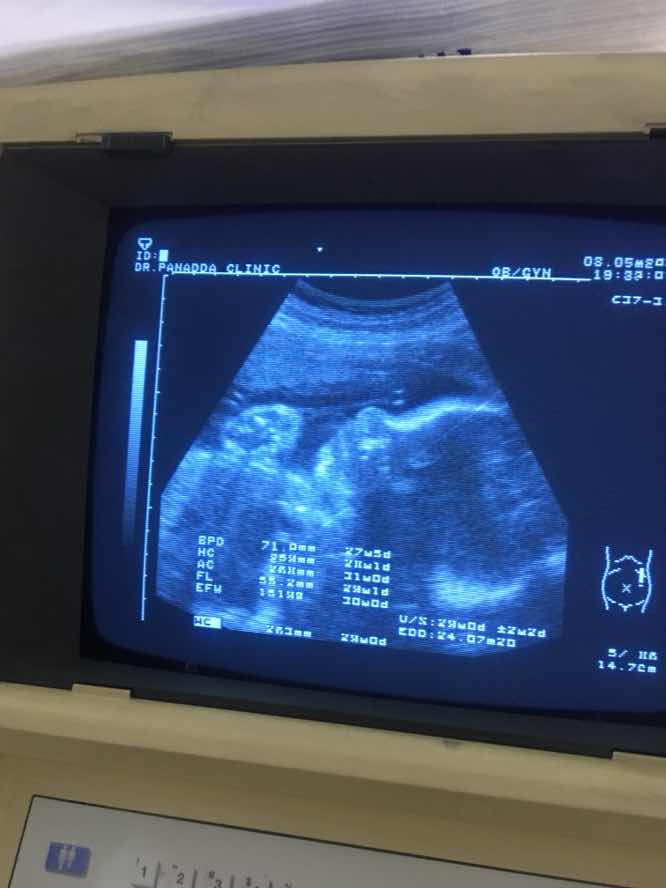

#ลูกสาว 29 กรกฎาคม 63